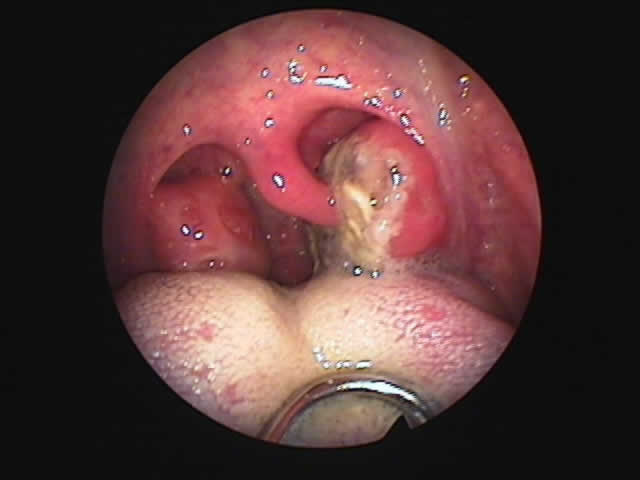

| 左扁桃術直後(31歳男性,6月9日) 数カ所針電極を刺入 | 白い部分が変性部位(6月11日) | 右扁桃術直後(7月7日) |